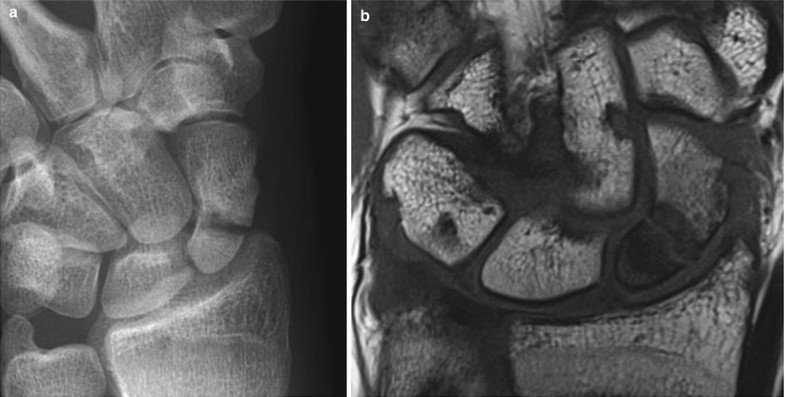

Scaphoid Fracture And Avascular Necrosis Springerlink